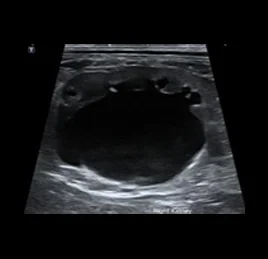

초음파 검사는 고주파 음파를 이용해 장기와 조직의 실시간 움직임을 영상으로 확인하는 비침습적 진단법입니다.

장기의 구조뿐 아니라 혈류, 운동성, 기능 변화까지 평가할 수 있어, 다양한 질환의 조기 발견과 모니터링에 효과적입니다.

📍초음파 진단 케이스

• 수신증

• 만성 신부전